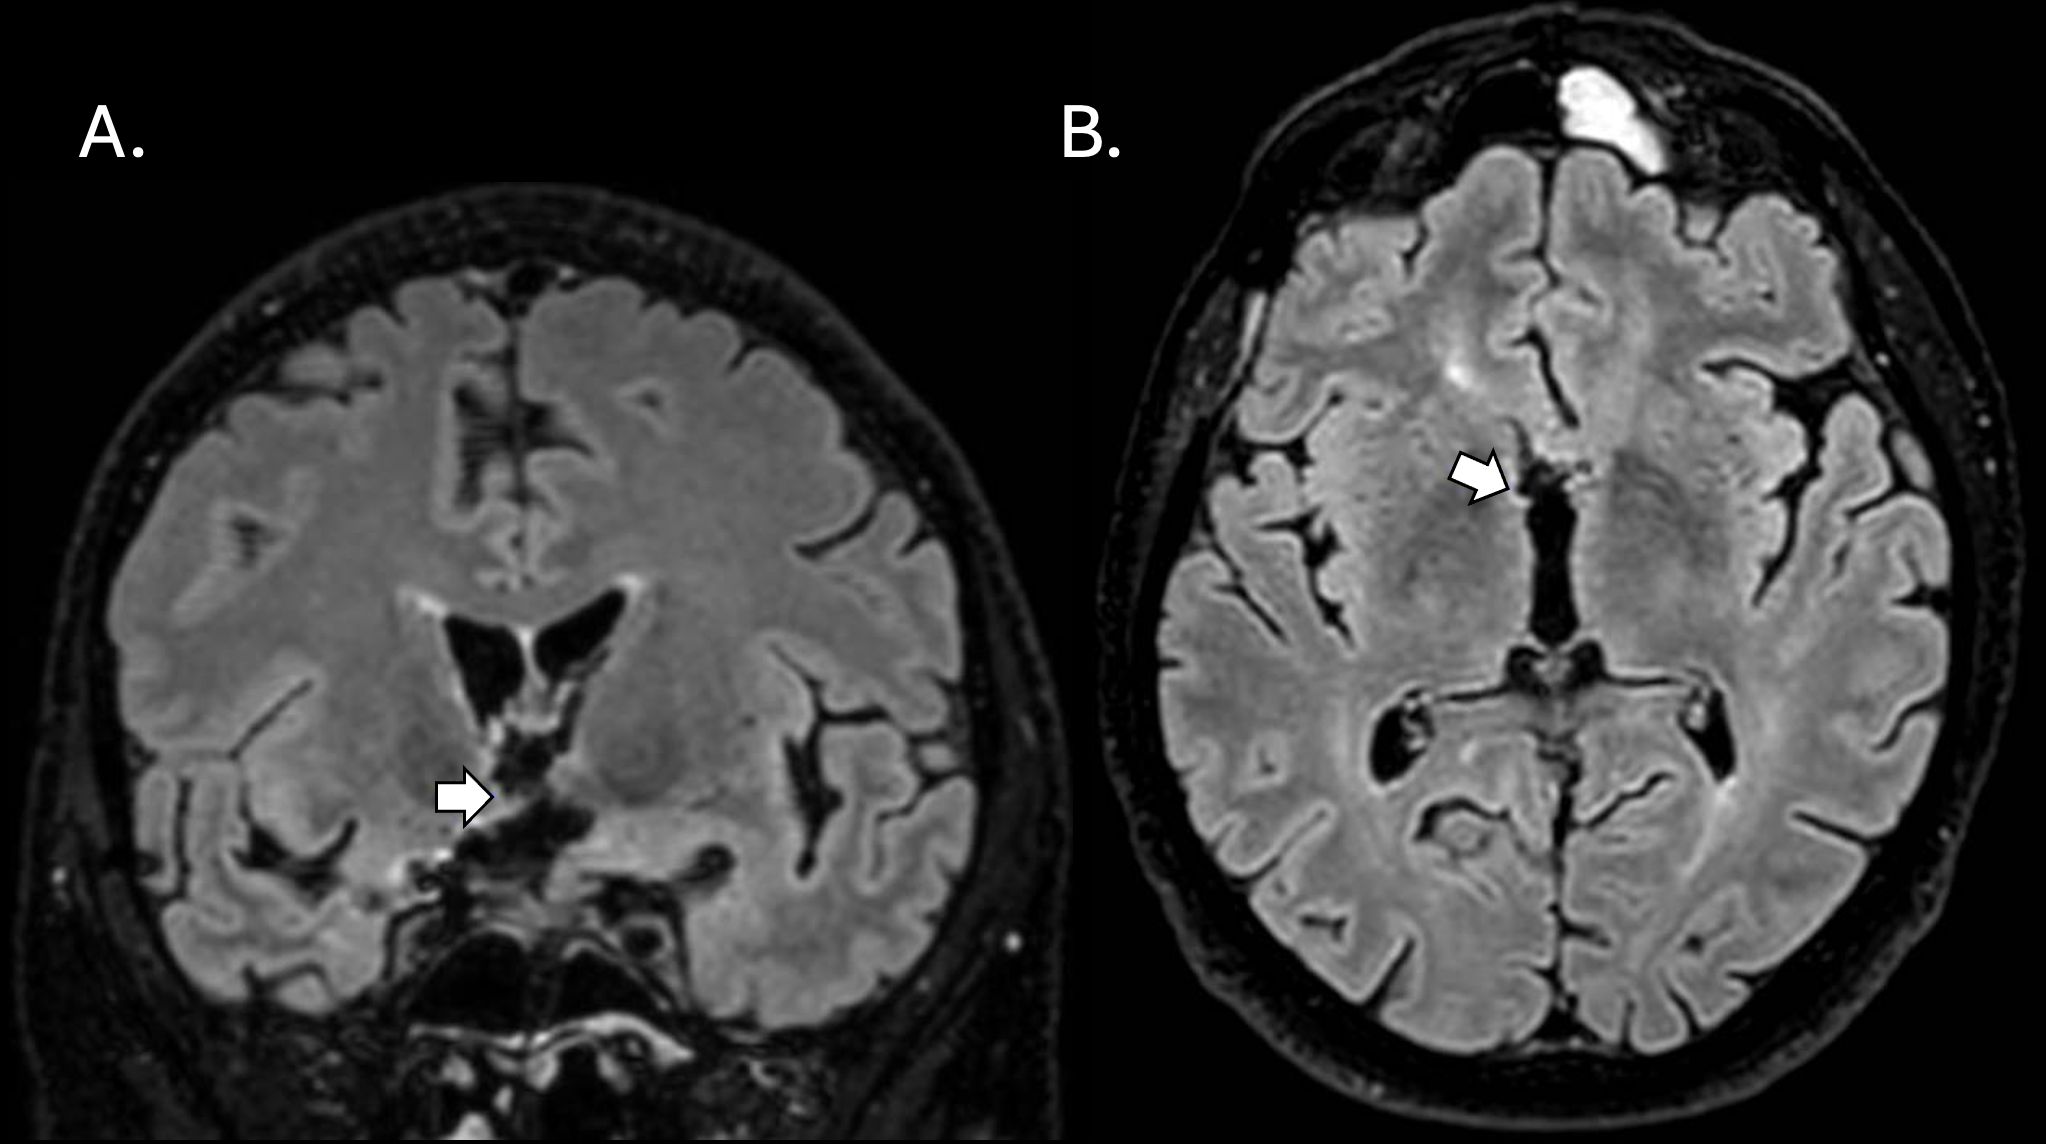

Due to these unexpected findings, a magnetic resonance image (MRI) scan of the brain was performed on the 7th postoperative day (Figure 2). The MRI revealed infarction in the genu rostrum of corpus callosum and bilateral oedema of the fornix anterior columns and the hypothalamus, in addition to ischemic changes nearby the surgical route (the anterior temporal and the basal frontal pole). No changes were observed in the hippocampus or the mamillary bodies. A follow-up MRI confirmed the infarctions. An MRI of the pituitary gland was also obtained, which showed no pathology in the pituitary gland.

Figure 2

Magnetic resonance imaging (MRI) FLAIR SPIR 1.2mm scans of the brain obtained at follow-up 1 month after the surgical clip ligation. White arrows in coronal (A) and axial (B) planes point to subacute infarction in the right hypothalamus. MRI scans were assessed by a specialist neuroradiologist (J.O.).